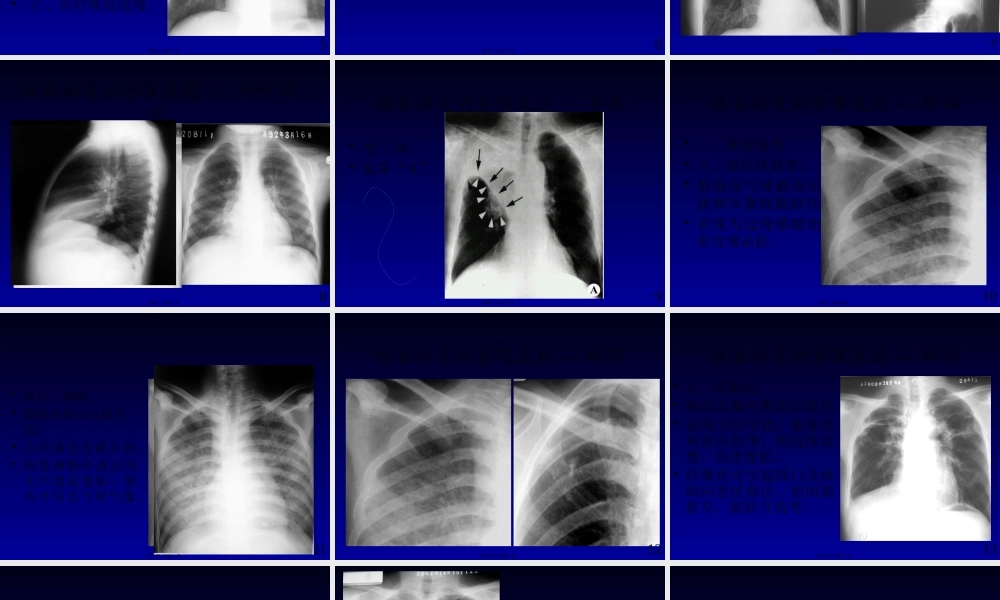

呼吸系统影像学诊断-----根本病变广东省人民医院影像医学部放射科赵振军1第一页,共四十一页。本节课内容•肺部根本病变的影像表现〔X线和CT〕•支气管病变•肺部病变•渗出性,增殖性、纤维化、钙化、空洞及空腔、肿块、肺间质的变化。•胸膜病变•纵隔病变•膈病变2第二页,共四十一页。根本病变的影像表现---支气管•一、支气管阻塞性改变•原因:1、支气管腔内。2、腔外。•支气管阻塞最常见病因有支气管腔内肿瘤、异物、结核及先天狭窄等。•淋巴结肿大是支气管外压性狭窄最常见的原因。•可引起阻塞性肺气肿、肺炎、肺不张。3第三页,共四十一页。根本病变的影像表现---支气管•1、阻塞性肺气肿:•支气管活瓣性狭窄,肺含气量增多。•分弥漫性和局限性•表现为1、肺透明度加大。2、肺纹理稀疏。3、占位改变:肋间隙增宽,膈肌下降、纵隔对侧移位等。4第四页,共四十一页。根本病变的影像表现---支气管•2、阻塞性肺炎:•支气管阻塞后继发肺部炎症。•A、阻塞区出现斑片状模糊影•B、该影特征为反复在固定部位出现•C、治疗吸收缓慢。5第五页,共四十一页。根本病变的影像表现---支气管•3、阻塞性肺不张:•支气管完全阻塞,肺内气体吸收,肺体积缩小。•一般分一侧肺、肺叶、肺段和肺小叶不张。6第六页,共四十一页。•直接征象:病变区域均匀密度增高影。•间接征象:体积收缩,如胸廓塌陷,肋间隙变窄,纵隔向患侧移位,肺门移位和膈肌升高等。根本病变的影像表现---不张7第七页,共四十一页。•轮廓征根本病变的影像表现---中叶不张8第八页,共四十一页。•“S征〞•反写“S〞根本病变的影像表现---不张9第九页,共四十一页。根本病变的影像表现---肺部•二、肺部病变•1、渗出性病变:•肺泡内气体被渗出液和少量细胞取代。•表现为边缘模糊的密度增高影。10第十页,共四十一页。•斑片、模糊•腺泡内渗出呈斑点状;•小叶渗出为斑片状;•肺段和肺叶渗出为大片状实变影,影内可见支气管气像。11第十一页,共四十一页。根本病变的影像表现---肺部•2、增殖性病变:•肺泡内细胞积聚,可形成肉芽肿。•表现为边缘较清楚的密度增高影,呈结节状、球形或肿块状。12第十二页,共四十一页。根本病变的影像表现---肺部•3、纤维化:•肺组织被纤维组织取代。•表现为结节状、索条状和斑块状等,但边缘清楚,高密度影。•纤维化可引起肺门及纵隔向患区移位,肋间隙狭窄,膈肌升高等。13第十三页,共四十一页。根本病变的影像表现---肺部•4、...

1、当您付费下载文档后,您只拥有了使用权限,并不意味着购买了版权,文档只能用于自身使用,不得用于其他商业用途(如 [转卖]进行直接盈利或[编辑后售卖]进行间接盈利)。

2、本站所有内容均由合作方或网友上传,本站不对文档的完整性、权威性及其观点立场正确性做任何保证或承诺!文档内容仅供研究参考,付费前请自行鉴别。